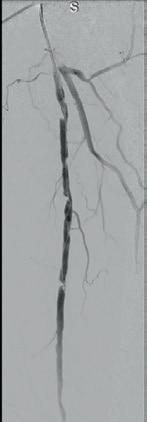

Shockwave E8 3mm x 80mm to the posterior tibial artery

The posterior tibial artery was successfully crossed first. The long-length posterior tibial artery disease was treated with a Shockwave E8 3.0mm x 80mm IVL catheter, with no pre-dilatation required. A total of 200 pulses were delivered along the length of the posterior tibial artery (Figure 3).

Shockwave E8 3mm x 80mm to the peroneal artery

Following this, the peroneal artery occlusion was successfully crossed. The longlength peroneal artery disease was treated with the same Shockwave E8 3mm x 80mm IVL catheter also with no pre-dilatation required. The remaining 200 pulses were

delivered across the length of the peroneal artery disease (Figure 3).